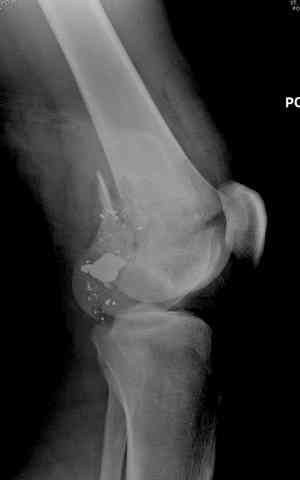

Здесь представлены несколько случаев лечения огнестрельного перелома

2 внутрисуставной перелом дистального бедра с удалением пули